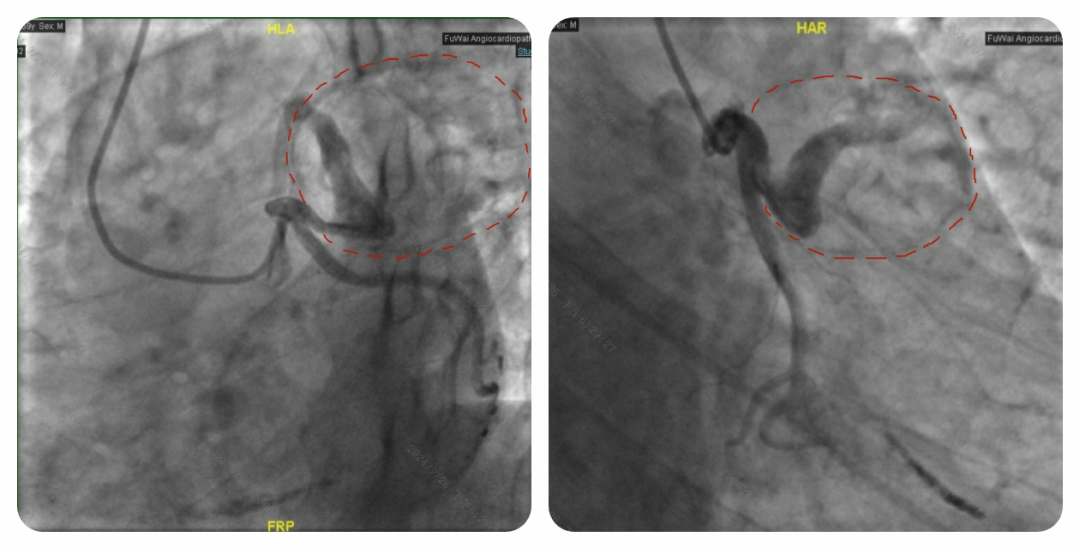

随着心脏超声、心脏 CT、心脏核磁以及冠状动脉造影检查结果的陆续出炉,答案终于浮出水面:它源自小迪的右冠状动脉。

这颗 “炸弹” 就像一个贪婪的 “侵略者”,当发现它时,其直径已将近 10 公分,源源不断的血液从右冠状动脉涌入其中,持续压迫着心脏,小迪也因此愈发难受。冠状动脉上出现如此巨大的 “炸弹”,极为罕见。一旦这个 “炸弹” 哪天突然 “爆炸”,小迪年轻的生命将岌岌可危。

为了确定是否需要为老秦实施外科手术 “排雷”,我们紧接着安排了冠状动脉造影检查。结果显示,虽然冠状动脉前降支被 “地雷” 包裹,但血管腔依旧通畅,“地雷” 没有对冠状动脉造成压迫,血管内的血液也没有渗漏到 “地雷” 内。